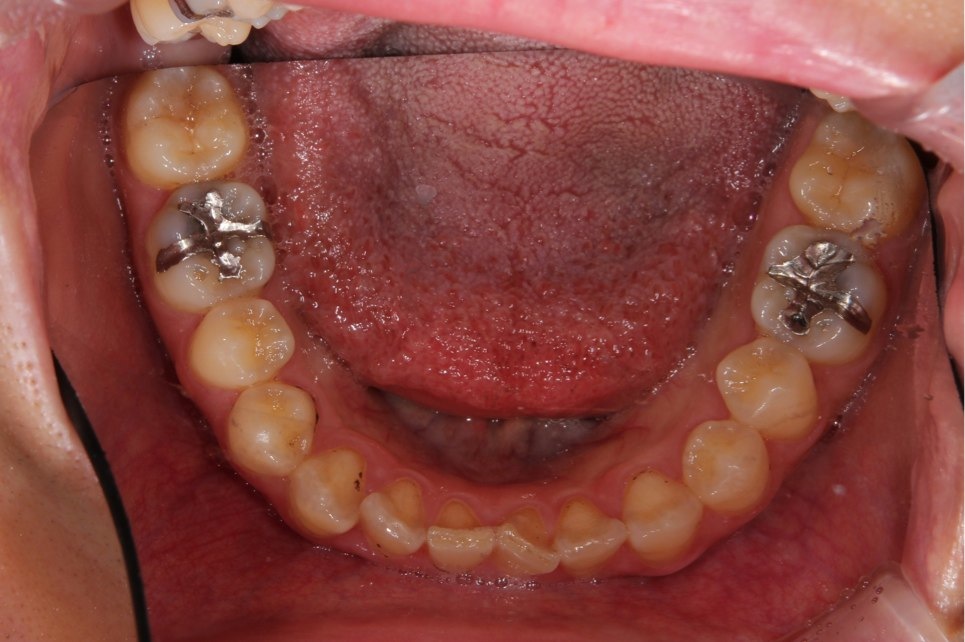

両奥に白い詰め物で治療してありますが、詰め物の周りが茶色に着色しています。また、本来の歯の形とはずいぶん違うみたいです。奥歯で噛んだ感じに違和感があるとの事でしたので、治療致しました。本来歯が持っている形をお口の中で作って行きます。

治療後です。どこを治療したのかわからないくらい『自然の歯』の様にできました。噛む時の違和感もなくなり、硬い物でも噛める様になりました。

左右奥歯のダイレクトボンディング

費用5万円×2本

リスクとして欠ける可能性がある(修復可能)。